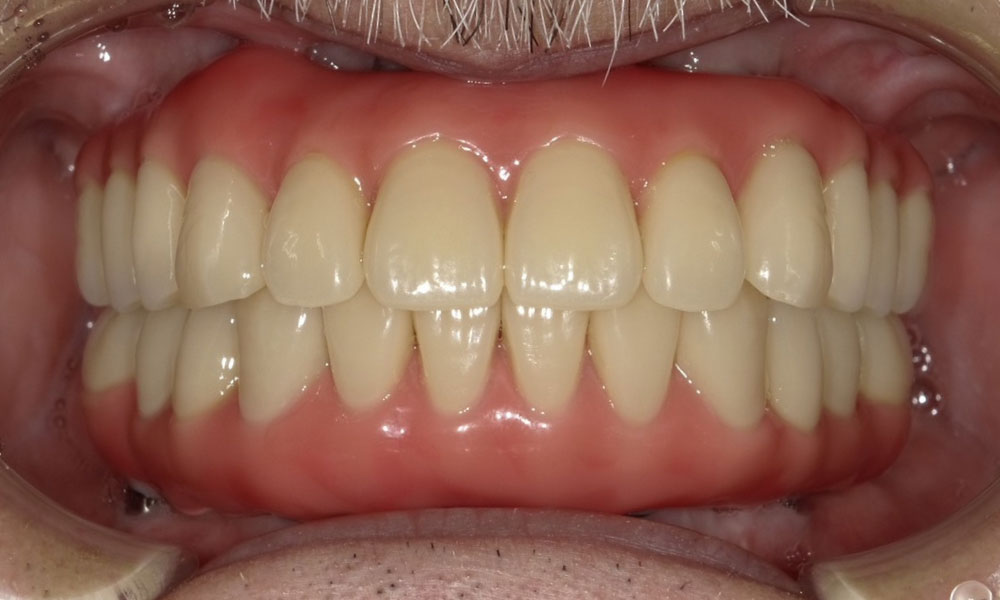

手術後口腔内